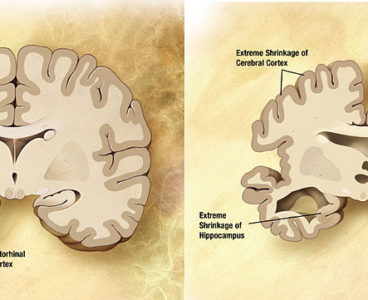

‘Silent Seizures’ Discovered in Patients With Alzheimer’s Disease

Study Reveals Potential New Strategy to Prevent Alzheimer’s Disease

Potential New Strategy to Prevent Alzheimer’s Disease

Taking a pill that prevents the accumulation of toxic molecules in the brain might someday help prevent or delay Alzheimer’s disease, according to scientists at Baylor College of Medicine, Texas Children’s Hospital and Johns Hopkins University School of Medicine. The study, published today in Cell Press journal Neuron, took a three-pronged approach to help subdue early…

Potential New Strategy to Prevent Alzheimer’s Disease

Taking a pill that prevents the accumulation of toxic molecules in the brain might someday help prevent or delay Alzheimer’s disease, according to scientists at Baylor College of Medicine, Texas Children’s Hospital and Johns Hopkins University School of Medicine. The study, published today in Cell Press journal Neuron, took a three-pronged approach to help subdue early…